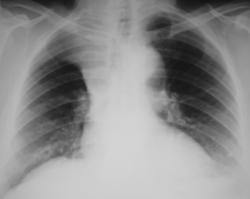

Иллюстрация 1. Цифровая флюорограмма, произведенная в прямой стандартной проекции. Справа определяется снижение прозрачности легочной ткани в области верхней части легочного поля с косой вогнутой границей, контур, которой довольно ровный и чёткий. Определяется некоторое расширение тени верхнего средостения вправо и некоторое увеличение интенсивности тени на уровне головки правого корня паратрахеально, возможно, за счет гиперплазированных лимфатических узлов. Пациент «взят на контроль», дообследован.

Иллюстрации 2, 3. Рентгенограмма в прямой стандартной проекции и фрагмент её с увеличением изображения. Теневые данные такие же, как и на флюорограмме, отмечается некоторое смещение трахеи вправо.